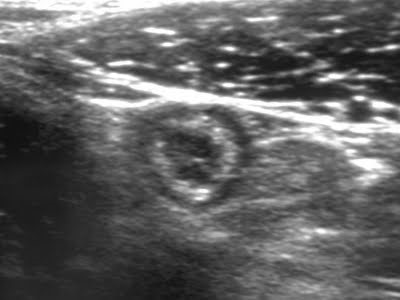

Abdominal ultrasonography

Abdominal ultrasonography is the first-line imaging modality in patients with acute abdominal pain suspected of appendicitis because it is inexpensive, rapid, easy to perform, and free of ionizing radiation; therefore, it is especially useful in children and pregnant women. The technique used is graded-compression ultrasonography to displace adjacent bowel loops.

Ultrasonographic findings of appendicitis include a blind-ended tubular structure arising from the cecum, with a diameter >6 mm, wall thickness >3 mm, absent peristalsis, non-compressibility, a target sign on transverse view, and a finger-like appearance on longitudinal view.

Figure 3. Ultrasonographic appearance of appendicitis